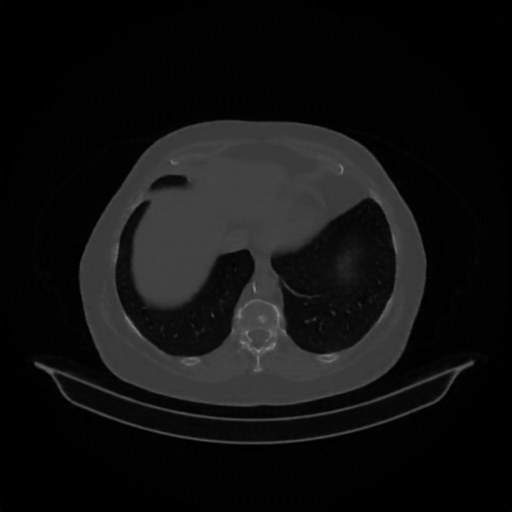

Original VENOUS CT scan

Full window (WL 1023.5, WW 4095 β†’ Low βˆ’1024, High +3071)

Lung window (WL -600, WW 1500 β†’ Low βˆ’1350, High +150)